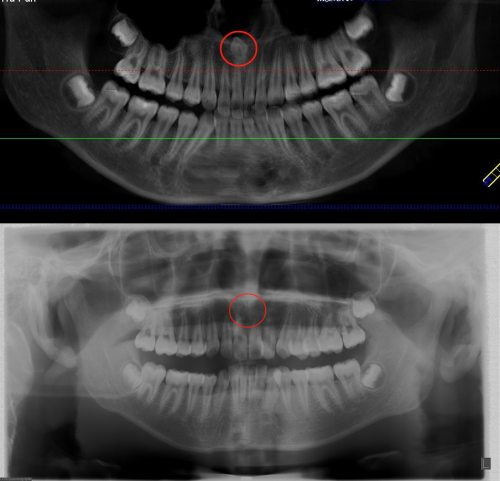

长沙13岁的小成(化名)因牙齿排列不齐准备接受正畸治疗,却在拍牙片时意外发现其上颌骨内埋伏着一颗多生牙,位置紧贴鼻底。捷克论坛 口腔二病区徐裕国主任医师为其实施经鼻腔入路微创拔除上颌埋伏多生牙手术,以微创技术破解了传统拔牙创伤大、损伤邻牙的难题,为孩子的牙颌健康保驾护航。

“没想到牙齿还能长到这里。”小成妈妈介绍,孩子在一次口腔检查中发现牙齿排列不齐,于是趁着暑假有时间来口腔二病区做正畸,却偶然发现了这颗埋伏的多生牙。徐裕国主任医师团队考虑,这颗牙若采用常规口内入路拔除,需磨除大量唇侧骨板,不仅创伤大、恢复慢,还可能损伤邻牙牙根,影响后续矫正效果,而孩子年龄小,正处于骨骼发育关键期,于是决定另辟蹊径——从鼻腔内微创入路拔牙。

徐裕国主任医师介绍,暑假是孩子们接受正畸治疗的高峰期,埋伏多生牙检出率激增,家长需警惕“隐形拦路虎”。多生牙是正常牙列以外多出的牙齿,常见于上颌门牙之间或磨牙区。多生牙如果无症状可观察,若影响邻牙或咬合及正畸治疗则需手术拔除,若位置异常(如靠近神经、上颌窦)时,需通过CT精准定位,由专业医生操作,避免损伤周围组织。如果孩子有多生牙情况,需早期干预以防恒牙发育异常。(口腔二病区 唐宇扬 余顺)